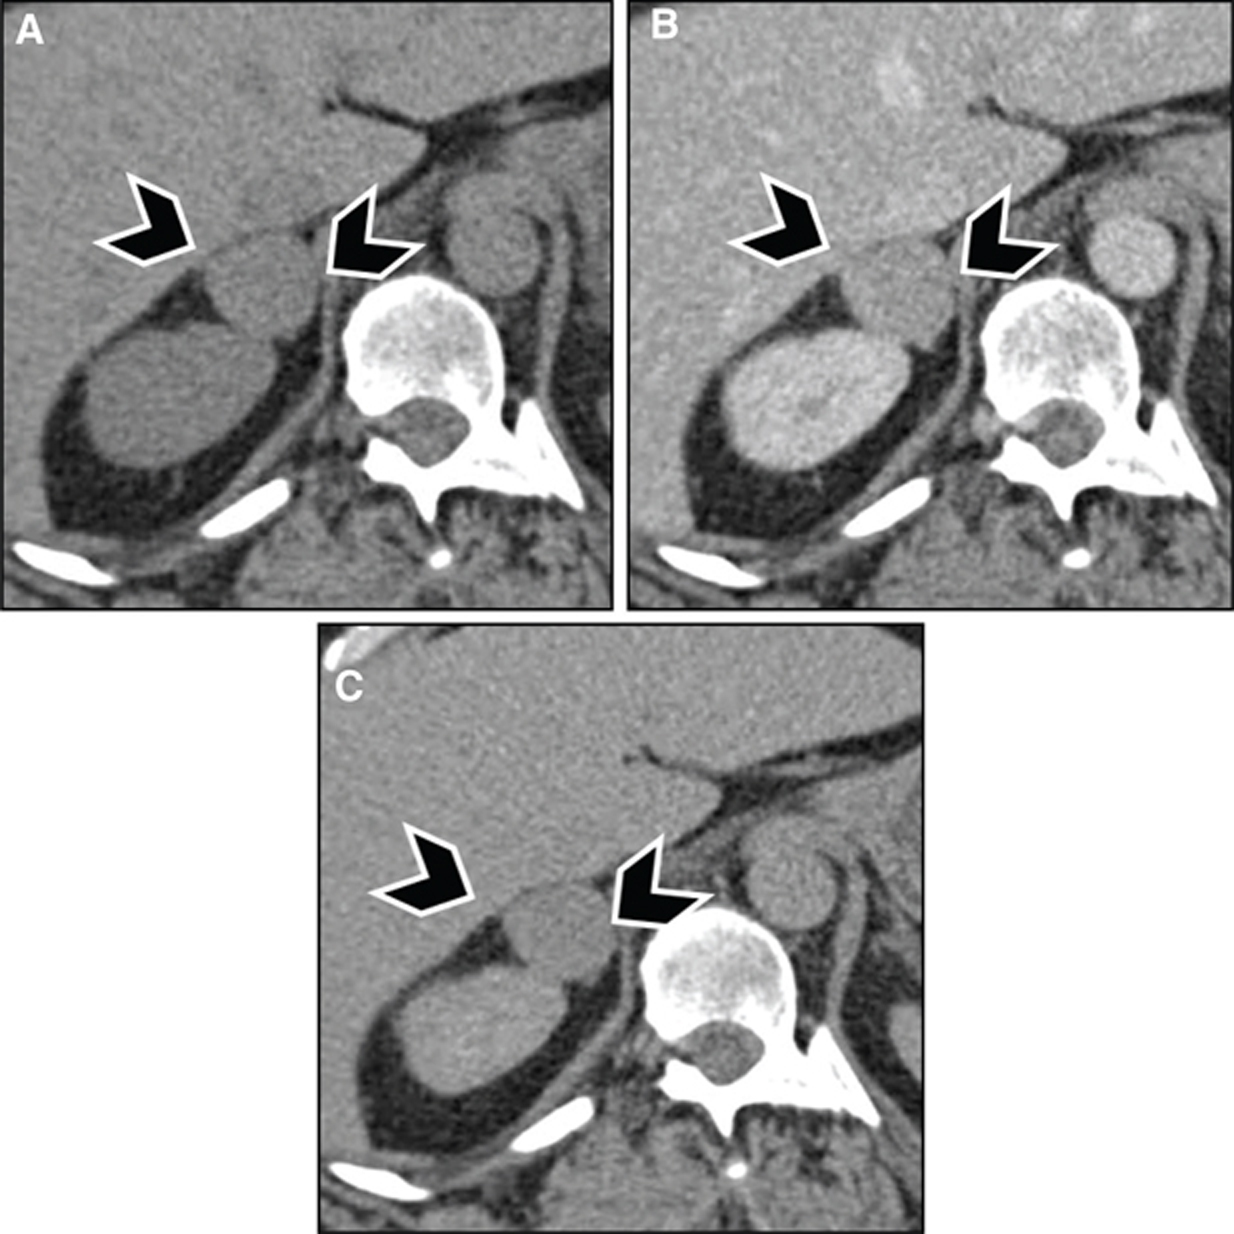

Fig 8

Figure 8 A 60-year-old woman with familial paraganglioma/pheochromocytoma syndrome status after right adrenalectomy with increased plasma metanephrine levels. (A) Previous whole body planar I-123 MIBG scan with attenuation-corrected SPECT, CT, and fused SPECT/CT images show increased uptake in multiple osseous lesions (white arrows). The patient was subsequently treated with I-131 MIBG therapy. (B) Ga-68 DOTATATE PET/CT maximum intensity projection (MIP) image of the skull vertex to the proximal thigh performed 5 years post-therapy because of increasing tumor markers shows widespread somatostatin receptor-positive bone metastatic disease with marked tracer uptake (arrows). (C) An F18-FDG PET/CT performed 1 week prior showed minimal to no uptake in corresponding osseous lesions.

Fig 9

Figure 9 A 55-year-old woman with metastatic paraganglioma having an initial Ki67 proliferation index of 25% and strong SSTR2A immunostain but without SDHB mutation on germline testing. (A) Ga-68 DOTATATE PET/CT maximum intensity projection (MIP) images of the skull vertex to the proximal thigh on the left show widespread somatostatin receptor-positive metastatic disease, with progressive disease on the right image with enlarging pelvic osseous lesions (arrows). (B) Ga-68 DOTATATE PET/CT axial fused PET/CT, axial PET, and sagittal fused PET/CT images show enlarging vertebral lesion (arrows) on the current study (top images) as compared to the prior (bottom images).